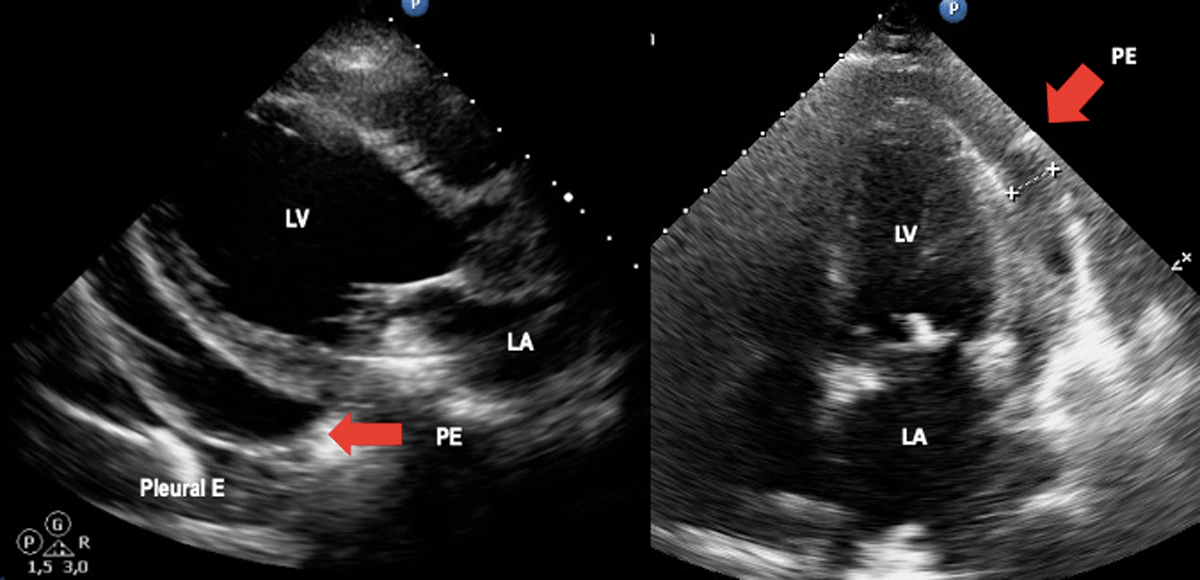

Figure 2

Acute Chagas disease. Arrows indicate pericardial effusion in heart failure due to Chagas disease. Image: Mariana Corneli. Reproduced with permission of the photographer.